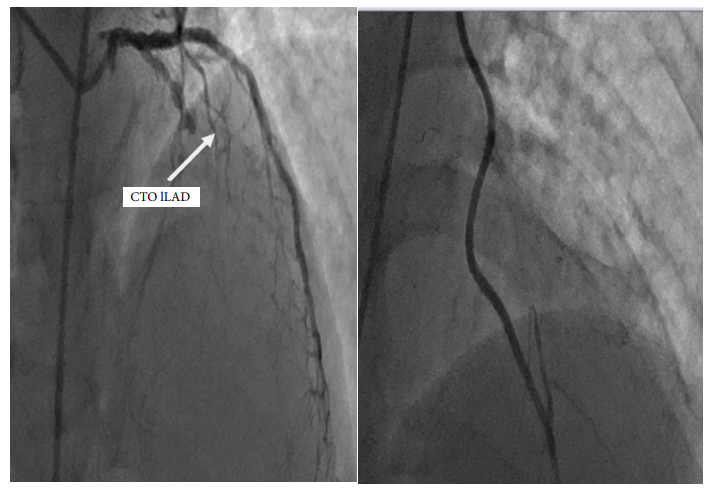

one case of HCR was described this patient presented with acute AWMI coronary anatomy showed osteal LAD with short left main underwent LIMA to LAD and long lesion with 99% RCA EF 40% procedure was uncomplicated hospital stay was 8 days Pic of HRS (123).

Figure 1: Pre and post procedure with LIMA CTO LAD

Figure 2: Pre and Post PCI OF RCA